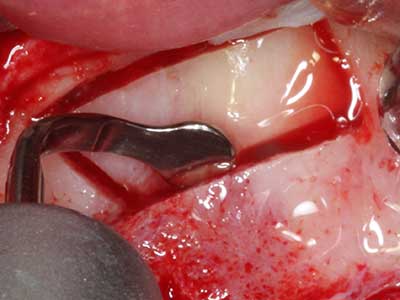

En la extracción de bloques óseos la piezocirugía también presenta ventajas adicionales: Además de la alta precisión en la osteotomía que ya se ha descrito antes, se ha comprobado que el uso de los delgados insertos de sierra resulta especialmente cuidadosas con el hueso. Frente a esto, sobre todo cuando se usan las fresas de Lindemann, cabe esperar pérdidas en la extracción significativamente más altas debido al mayor grosor de la parte frontal del cabezal (Lakshmiganthan, Gokulanathan et al. 2012). La separación basal que se necesita en particular en los injertos de bloque extraídos de forma retromolar se ve facilitada mediante sierras perpendiculares especialmente previstas a tal fin, lo que permite considerar que la cirugía piezoeléctrica es un procedimiento preciso y seguro para la obtención de bloques de hueso en el área retromolar (Happe 2007) (fig. 1-12).

Si es preciso realizar intervenciones quirúrgicas en las que el hueso está en contacto directo con estructuras sensibles, como son los vasos sanguíneos o los nervios, los instrumentos rotativos presentan un enorme potencial de provocar lesiones iatrogénicas. Así, precisamente en la representación de nervios después de una lesión iatrogénica, o en el transcurso de la lateralización de un nervio para resecciones, reconstrucciones o incorporación de implantes, los equipos piezoeléctricos pueden resultar muy útiles para preparar la tapa ósea y retirar las partes de tejido duro cercanas al nervio (fig. 17-20). Por lo general, un ligero contacto del cordón nervioso con el inserto piezoeléctrico no tiene consecuencia alguna; ahora bien, un procedimiento poco cuidadoso con movimientos tipo sierra o piezas de trabajo sobre la base ósea aún existente puede provocar lesiones nerviosas temporales o incluso permanentes. Con todo, el riesgo de sufrir una lesión de este tipo se considera significativamente inferior que en los casos en los que se utilizan sierras y fresas (Pereira, Gealh et al. 2014).